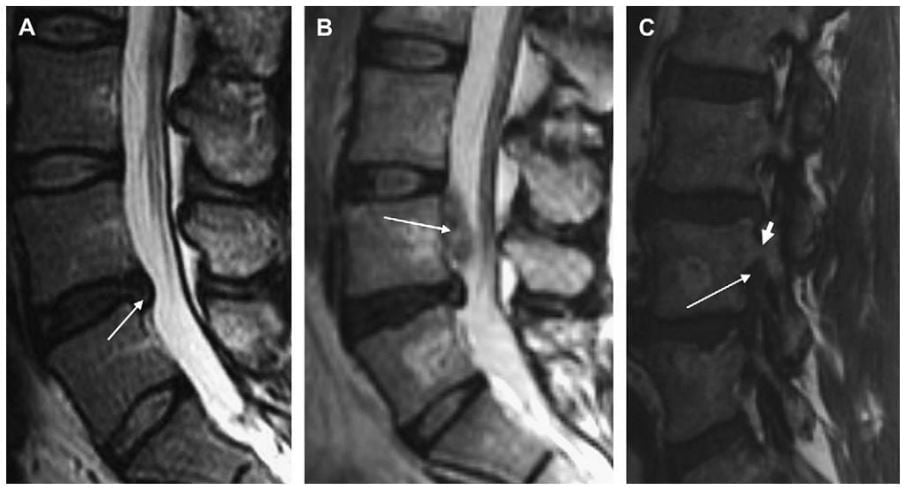

Hình 5. Hình MRI sagittal cột sống thắt lưng cho thấy đĩa đệm bình thường (A), protrusion L5-S1 (B), extrusion kèm di lệch xuống dưới ngang mức L5-S1 (mũi tên) (C). Các đường trắng chỉ ra bờ trên và bờ dưới đĩa đệm L5-S1 ở hình B và C. Protrusion không vượt qua chiều trên – dưới đĩa đệm trên hình sagittal (B), trong khi extrusion vượt qua bờ này (C).

Hình 7. Hình sagittal T2W cột sống thắt lưng minh hoạ protrusion (mũi tên trắng) (A). Gni nhận độ lan theo chiều trên duới không vượt qua bề mặt thân sống trên và duới. Extrusion đĩa đệm có lan chất đĩa đệm xuống dưới vượt qua giới hạn bề mặt trên của S1 (mũi tên trắng) (B). Mảnh đĩa đệm (mảnh rời) cũng nhìn thấy ở phía dưới của phần extrusion (đường chấm trắng).